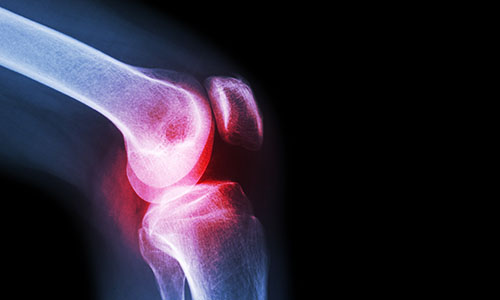

- Experts in hip and knee surgery (replacement, revision, keyhole surgery)

- Knee replacement

- Knee arthroscopy

- Robotic knee replacement (total and partial)

Are you suffering from a niggling knee injury or a sore hip?

Many people with a joint issue, whether it's a niggling knee injury or a sore hip, simply tolerate the pain or discomfort and accept the limitations this brings. In many cases that's unnecessary. Worn out joints can often be repaired or replaced. Orthopaedic surgery can give you a new lease on life, but it’s a big decision and you need to feel confident in your surgeon.